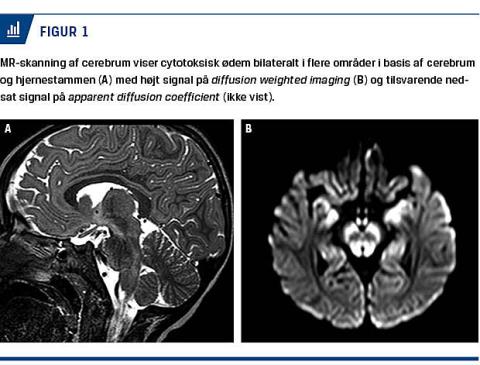

De næste døgn sås der mindre udtalt encefalopati. MR-skanning af cerebrum (Figur 1) viste diffuse højsignalforandringer, hvilket er foreneligt med cytotoksisk ødem centralt i pons, medulla oblongata, thalamus og globus pallidus. Han blev udskrevet efter ti døgns indlæggelse. Urinmetabolisk screening og molekylærgenetisk undersøgelse bekræftede diagnosen intermitterende MSUD.

Patienten blev overflyttet til Rigshospitalet pga. tiltagende encefalopati og forværret metabolisk acidose. Der var multiorgansvigt med behov for respiratorbehandling, inotropi og P-dialyse. En MR-skanning af cerebrum viste diffuse højsignalforandringer centralt i pons, mesencefalon, basalkerner, mesialt temporalt og kortikalt bilateralt.